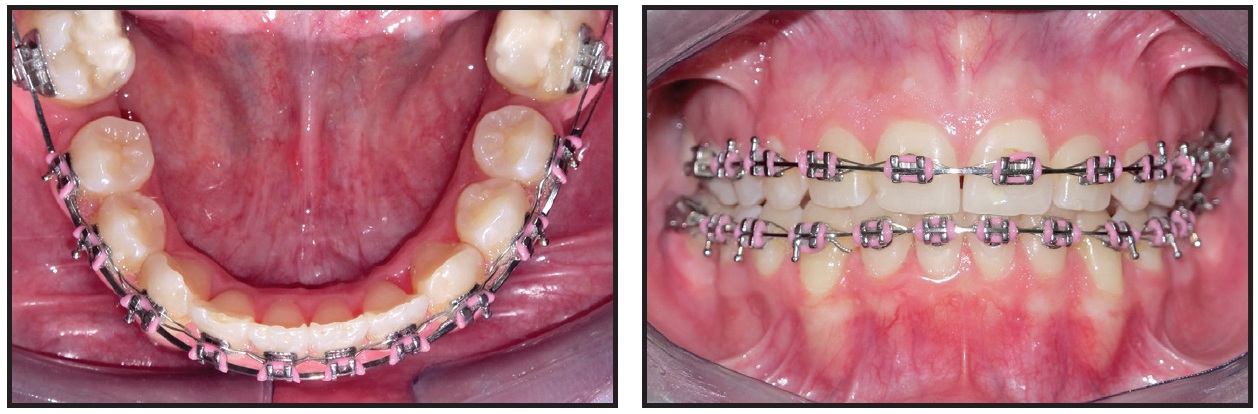

Two months later, brackets were bonded in the upper arch (Fig. 5); the leveling stage was started with an .014" nickel titanium archwire and finished five months later with an .019" × .025" stainless steel wire.

Retraction mechanics were applied to distalize the lower buccal segments and protract the second molars (Fig. 6). Three months later, the lower premolars and canines had been retracted enough to relieve the anterior crowding and allow anterior alignment without proclination (Fig. 7).

Fig. 5 Two months after surgery, upper brackets bonded and leveling initiated with .014" nickel titanium archwire.

Fig. 6 Retraction mechanics applied to distalize lower buccal segments and protract second molars.

Fig. 7 Three months later, lower anterior teeth bonded and space closure initiated in upper arch.

Space closure was started simultaneously in the upper arch. Five months later, leveling and alignment of the lower arch were completed on an .019" × .025" stainless steel archwire.